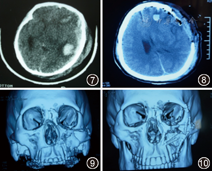

患者男性,31岁,因"高处坠落致颅面部损伤7 h"急诊入院。患者外伤后即昏迷。神经外科检查:心率140次/min、呼吸36次/min、血压80/50 mmHg(1 mmHg=0.133 kPa)。中度昏迷,左侧瞳孔散大,对光反射消失,右侧巴宾斯基征(+),GCS 7分,右侧脑脊液鼻漏及耳漏。口腔颌面外科检查:左侧颧面部淤血肿胀,左眼眶下缘有台阶感,左侧上颌骨可及异常动度,咬合关系紊乱。CT检查:左额颞顶部新月型高密度影,中线明显右移,左上颌骨、颧骨、颧弓、鼻骨多发骨折。

诊断:重度颅脑损伤、左侧额颞顶部硬脑膜下血肿、小脑幕裂孔疝,创伤性失血性休克,面部多发骨折。

治疗过程:该患者颌面部损伤属于闭合性,暂时不危及生命,但存在重症颅脑损伤,颅内血肿已致脑疝形成,随时可因脑疝致脑干功能衰竭引起死亡,因此必须立即开颅手术才能挽救患者生命。因此在迅速纠正失血性休克后,急诊全麻下顺利实施"开颅血肿清除术+去骨瓣减压术",术后当日患者转为浅昏迷,左侧瞳孔缩小,对光反射减弱,右侧巴宾斯基征(+),GCS 10分。术后3 d苏醒,双侧瞳孔等大等圆,对光反射灵敏,右侧巴宾斯基征(-),GCS 13分。4周后病情稳定,转口腔颌面外科全麻下行左面部多发陈旧性骨折切开+复位内固定术。6个月后复诊,GOSⅤ级(图7,图8,图9,图10)。